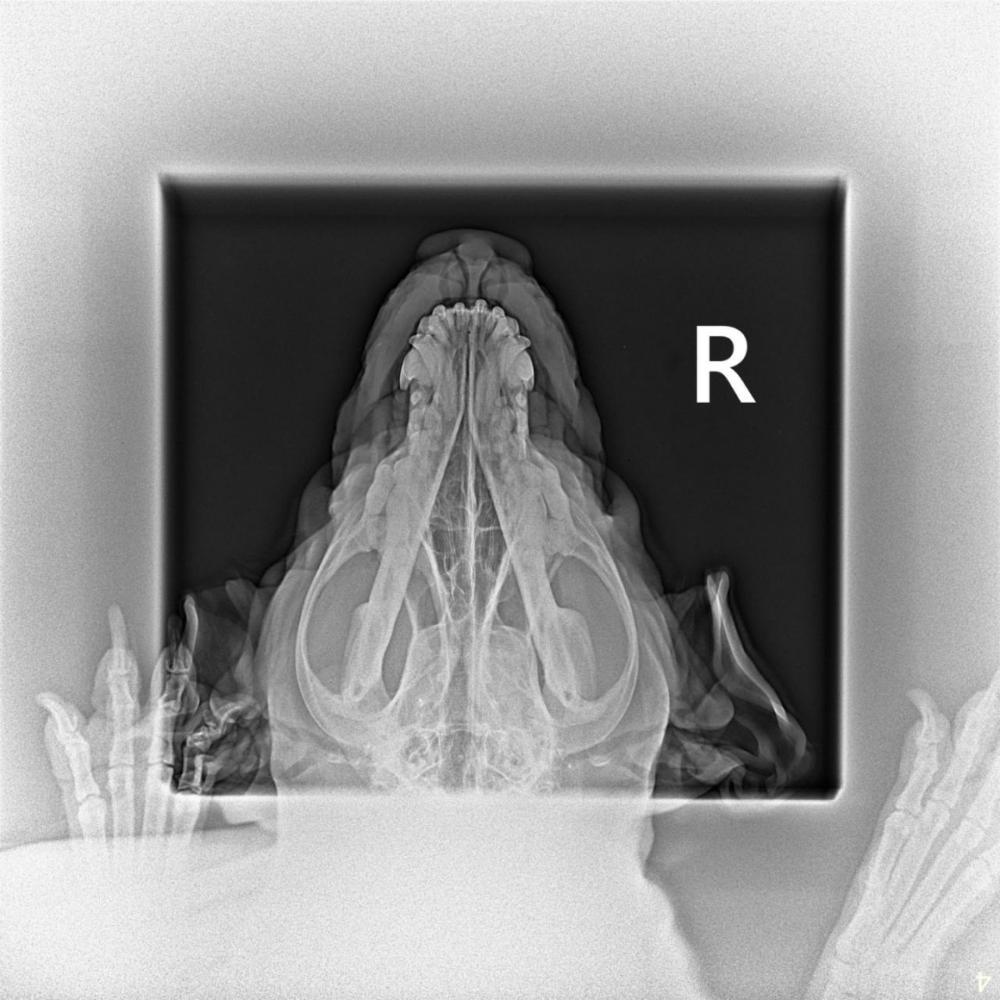

Анила Опубликовано 19 ноября, 2025 Опубликовано 19 ноября, 2025 В 01.08.2023 в 17:19, Ira&Ozzy сказал: Добрый день, поискала на форуме и не наш ответ на свой вопрос. У собаки опух нос, сам пятачок, и один проход сужен немного, были у ветеринара- озвучили подозрение на аллергию или кто-то укусил, прописали преднизолон по схеме. Спустя два дня приема опухлость немного уменьшись, но нос прорвало в одном месте будто прыщ, вышло немного гноя. Может кто-то стаскивая с таким? Что это может быть? Здравствуйте!!!! Помогите!!! У нас такая же проблема!!! Расскажите пожалуйста, что у Оззи было! Нам ставят НЕОПЛАЗИЯ носовых ходов ( рак). Сделали рентген! Ничего не говорят! Записались на КТ, ждём!